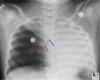

Is this a proper placement of a central line?

* No, the tip (smaller red arrow) is within the right ventricle. Pt will probably experience PVCs. * The catheter tip should lie between the most proximal venous valves of the subclavian or jugular veins and the right atrium.